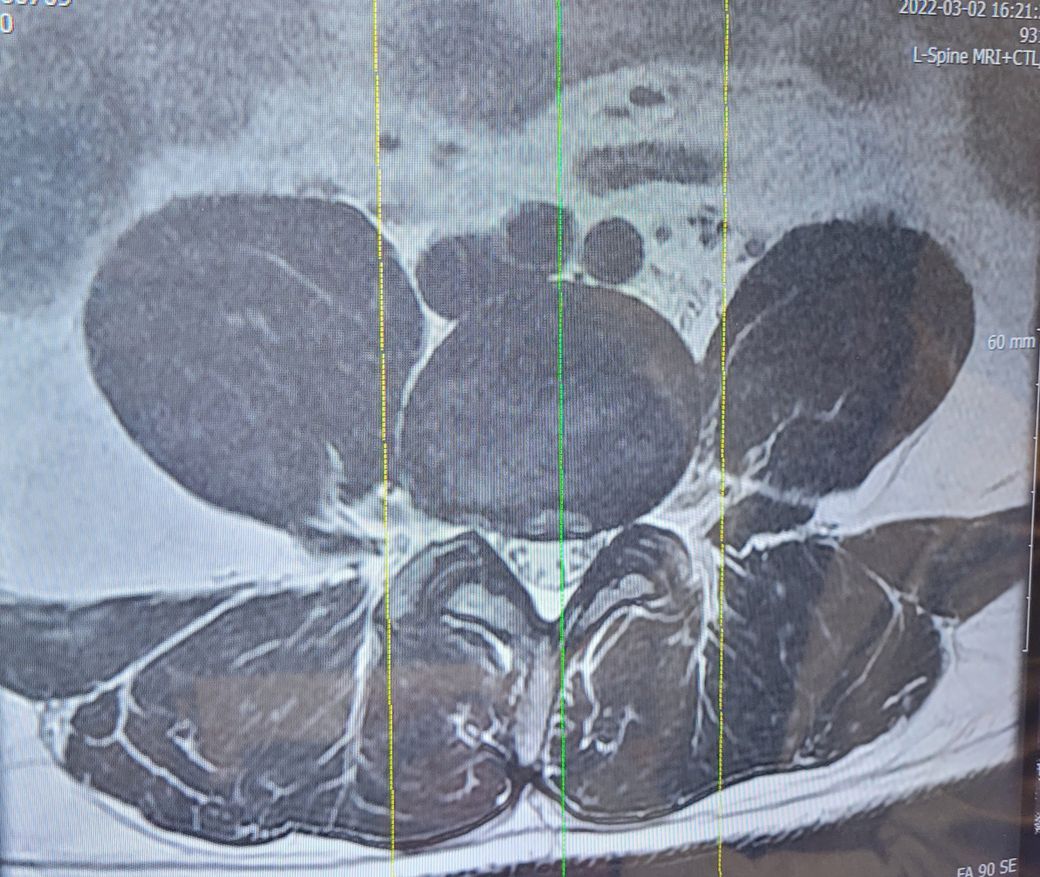

오늘 MRI를 찍었는데 4,5번 디스크가 나와서 신경을 눌려서 그렇다고 수술을 하라고 하던데...

• 1번 째 사진

MRI상 디스크 탈출로 인한 증상으로 보입니다.